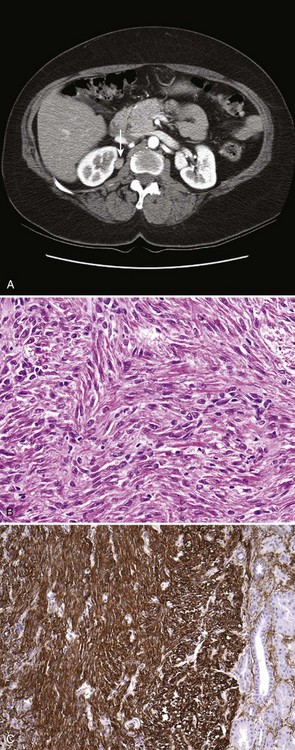

Renal leiomyomas have a characteristic appearance of a small exophytic renal mass with or without enhancement arising from renal capsule, but conclusive radiologic differentiation from RCC is not possible (Fig. 51–11A) (Steiner et al, 1990; Derchi et al, 2008).

Figure 51–11 Renal leiomyoma. A, CT scan with characteristic appearance of a small renal mass arising from the renal capsule. B, Medium-power magnification shows uniform spindle cells with thin cigar-shaped nuclei, without any pleomorphism. C, Strong positive immunohistochemical staining with smooth muscle actin in the leiomyoma. Note lack of smooth-muscle actin staining in the normal renal tubules on the right.

Grossly, leiomyomas are well encapsulated and range from purely cystic to mixed solid/cystic or solid in appearance. Histologic examination reveals intersecting fascicles of smooth muscle with no evidence of hypercellularity, pleomorphism, mitotic activity, or necrosis (see Fig. 51–11B) (Steiner et al, 1990; Tamboli et al, 2000). Immunohistochemical stains confirm the smooth muscle nature of the tumor with strong diffuse positive staining for smooth muscle markers desmin and caldesmon (see Fig. 51–11C) (Romero et al, 2005). Large lesions have traditionally been managed with radical nephrectomy, but nephron-sparing approaches should be considered for peripherally located small lesions.